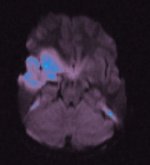

Meine MRT

Aufnahmen:

T2-gewichtetes MRT |

Organisches Gewebe enthält viel Wasser und Fett. Diese Stoffe

bestehen im Mensch aus ca. 63% Protonen. Setzt man Protonen einem

magnetischen Feld aus, schwingen sie entsprechend der Feldstärke.

Diese absorbierte Energie geben sie wieder ab, was man messen kann.

Die Signalstärke wird durch jedes Proton leicht variiert.

Läßt

man ein zusätzliches Magnetfeld einwirken, das in Stärke und Lage

variiert wird, läßt sich durch die unterschiedliche Resonanz der

Felder pro Ort eine elektromagnetische Strahlung messen. Daraus kann

man ein 3D-Bild berechnen.